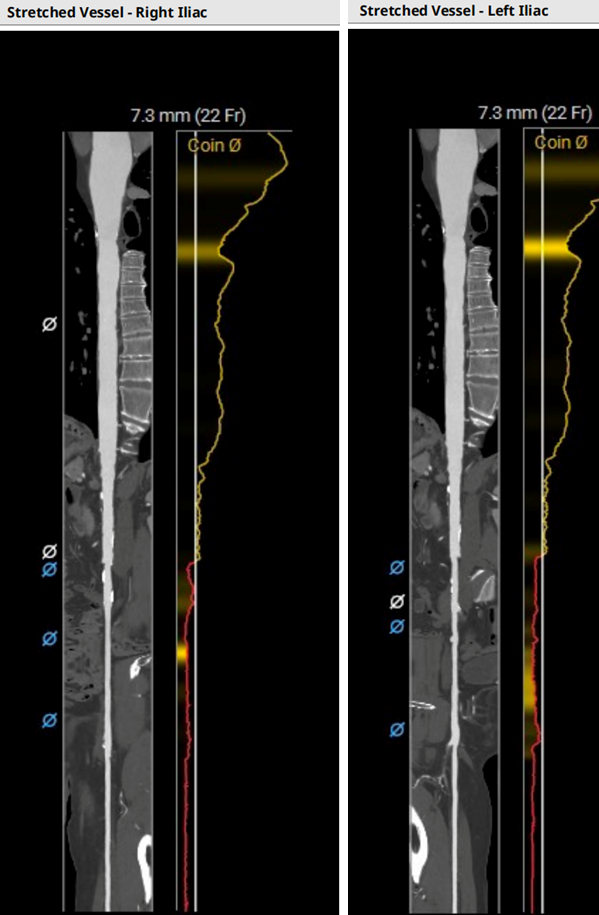

血管入路评估:腹主动脉及髂总动脉可见散在钙化,右侧髂外动脉最细5.8 mm(平均径5.9 mm),左侧髂外动脉最细5.8 mm(平均径6.1 mm)。双侧股动脉分叉点较高。23#瓣膜选用22F大鞘。